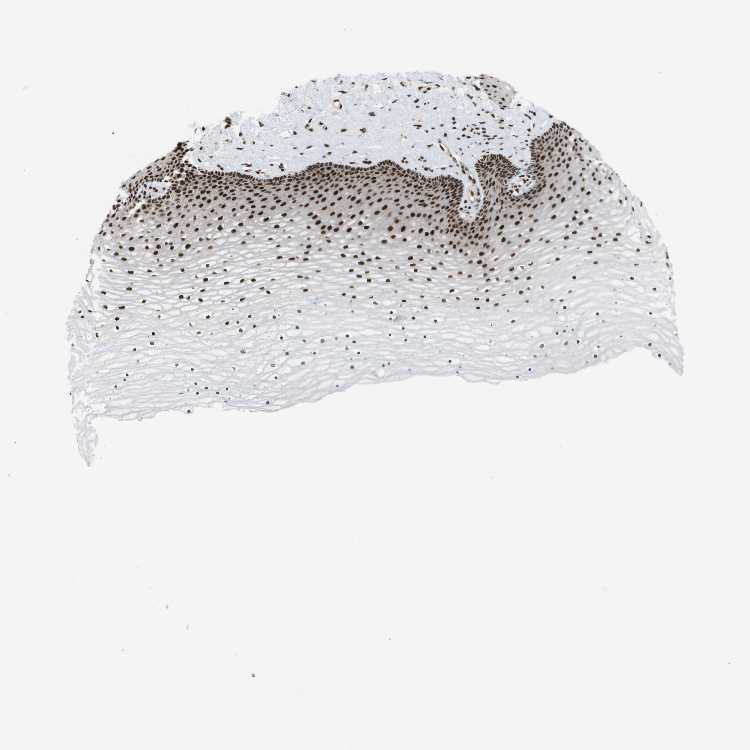

CERVIX - Antibody stainingi

Antibody staining in the annotated cell types in the current human tissue is reported as not detected, low, medium, or high, based on conventional immunohistochemistry profiling in selected tissues. This score is based on the combination of the staining intensity and fraction of stained cells.

Each image is clickable and will lead to virtual microscopy that enables deeper exploration of all samples and also displays staining intensity scores, fraction scores and subcellular localization as well as patient and tissue information for each sample.

Antibody HPA017224

Glandular cells High

Squamous epithelial cells High